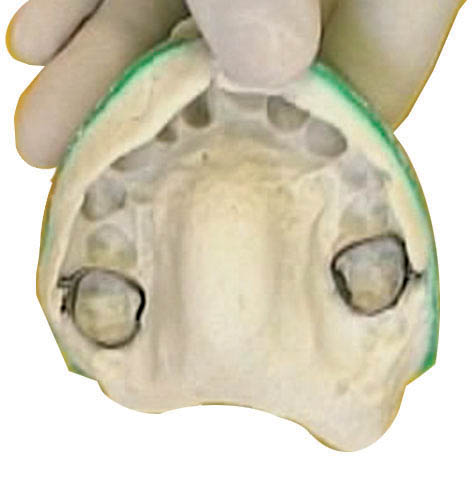

اگر نیاز به ساختن لینگوال آرچ یا پالاتالبار دارید (مثلاً برای جلوگیری از حرکت مزیالی مولرها و حفظ فضای E) باید بندها را در جایگاه خود بگذارید و با گیج ارتفاع آن را تنظیم کنید، بعد یک قالب pick-up از روی آنها با آلژینات میگیرید. سپس بندها را خارج و درون آلژینات میگذاریم (شکل 60-1) و گچ آن را میریزیم. بدینصورت بندها به روی کست گچی منتقل میشوند. حال این قالب را به لابراتوار بفرستید تا پالاتالبار یا لینگوال آرچ بسازند. بهتر است بندها را یک درجه بزرگتر بگیرید تا زمانی که به یکدیگر لحیم میشوند جازدن روی دندانها مشکل نشود.

شکل 60-1: قالب pick-up از بندها جهت ساخت لینگوال آرچ و پالاتال بار